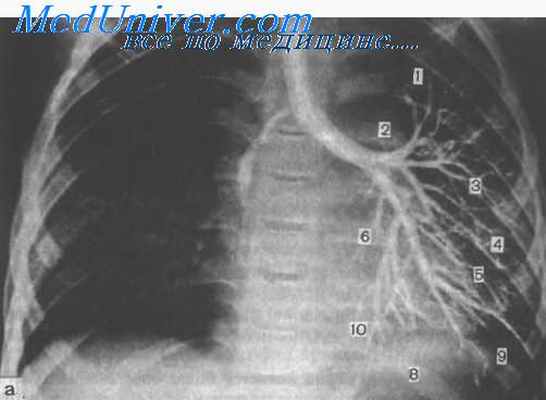

Гемоторакс

Скопление крови в полости плевры наблюдается почти при каждой травме груди. Источником кровотечения чаще всего бывают межреберные - сосуды, сосуды легких, реже сердцами средостения. Объем гемоторакса варьирует в широких пределах — от нескольких миллиметров до нескольких литров. Небольшое количество крови (менее 150—200 мл) не удается диагностировать ни клиническими, ни рентгенологическими методами.

Излившаяся в плевральную полость кровь обычно свертывается, а затем вследствие фибринолиза вновь становится жидкой. Однако при большом гемотораксе часто образуются сгустки (свернувшийся гемоторакс), которые препятствуют расправлению легкого и могут нагнаиваться. Патологическое влияние гемоторакса двоякое: кровопотеря как таковая и сдавленис органов груди. В зависимости от объема кровопотери в той или иной мере выражена гиповолемия, которая всегда усугубляет дыхательные и циркуляторные расстройства. Это следует обязательно учитывать при составлении плана лечебных мероприятий. Быстрое на-растанисгемоторакса и повторное появление крови после ее аспирации всегда свидетельствуют о продолжающемся кровотечении н могут служить показанием к торакотомии.

Массивный гемоторакс приводит к коллапсу легкого и смешению средостения. Как и пневмоторакс, это обусловливает выраженные нарушения дыхания и работы сердца. Гемопневмоторакс представляет собой синдром сочетанного повреждения воздухоносных и кровеносных путей. Его роль в патогенезе травмы груди такая же, как и каждого из его компонентов в отдельности.

Для уточнения предварительно поставленного по симптоматике диагноза могут быть использованы такие инструментальные исследования, как УЗИ грудной клетки, ее рентгенография, а также торакоскопия. Присутствие крови в диагностической пункции плевральной полости является однозначным свидетельством ее скопления внутри.

Диагноз устанавливается на основании доступных анамнестических сведений, клинических проявлений, результатов физикального, лабораторного и инструментального (если позволяет состояние больного и есть хотя бы минимальный запас времени) обследования. Стандарт экспресс-диагностики в данном случае включает обзорную рентгенографию, КТ, УЗИ, плевральную пункцию, диагностическую торакоскопию и клинический анализ крови в режиме cito (лат. «срочно»).